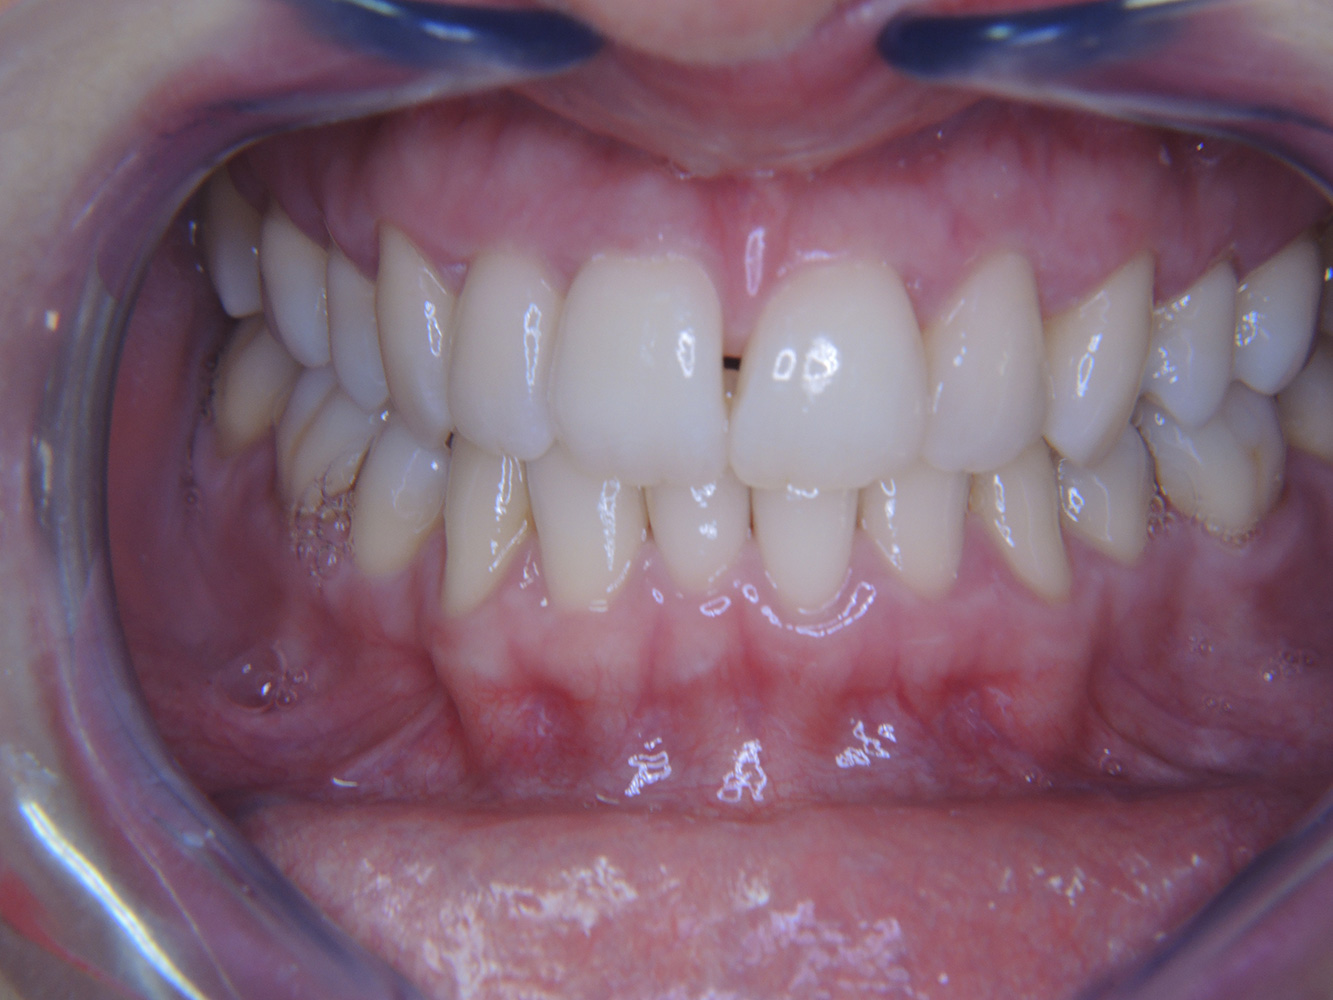

Una paziente diabetica di 51 anni con una buona igiene orale si presenta per una seduta di prevenzione. I valori di glicemia sono stabili con HbA1c = 6,2%, per cui si ritiene che la sua condizione possa essere sufficientemente gestita con la metformina (un farmaco per il trattamento del diabete). La paziente non presenta restauri esistenti o precedenti patologie orali. Sulla base dei referti disponibili si può constatare una gengivite nonostante una condizione altrimenti stabile.

Sebbene i parametri di salute generale e orale siano stabili, la paziente necessita di una seduta di prevenzione personalizzata per via della sua patologia di base. Il diabete mellito è sempre associato a un rischio maggiore di parodontite (12), che tuttavia può essere tenuto sotto controllo con un buon trattamento medico. Il monitoraggio regolare della HbA1c fornisce indicazioni sull'andamento del livello di glicemia nelle ultime otto-dodici settimane, un valore HbA1c ≥ 6,5% indica la presenza di diabete mellito.

Anche se lo stato di salute orale della paziente non indica un particolare bisogno di un intervallo di richiamo più ravvicinato, si consigliano comunque due sedute di profilassi l'anno in considerazione dei rischi legati al diabete mellito e della sua stretta correlazione con un rischio aumentato di parodontite.